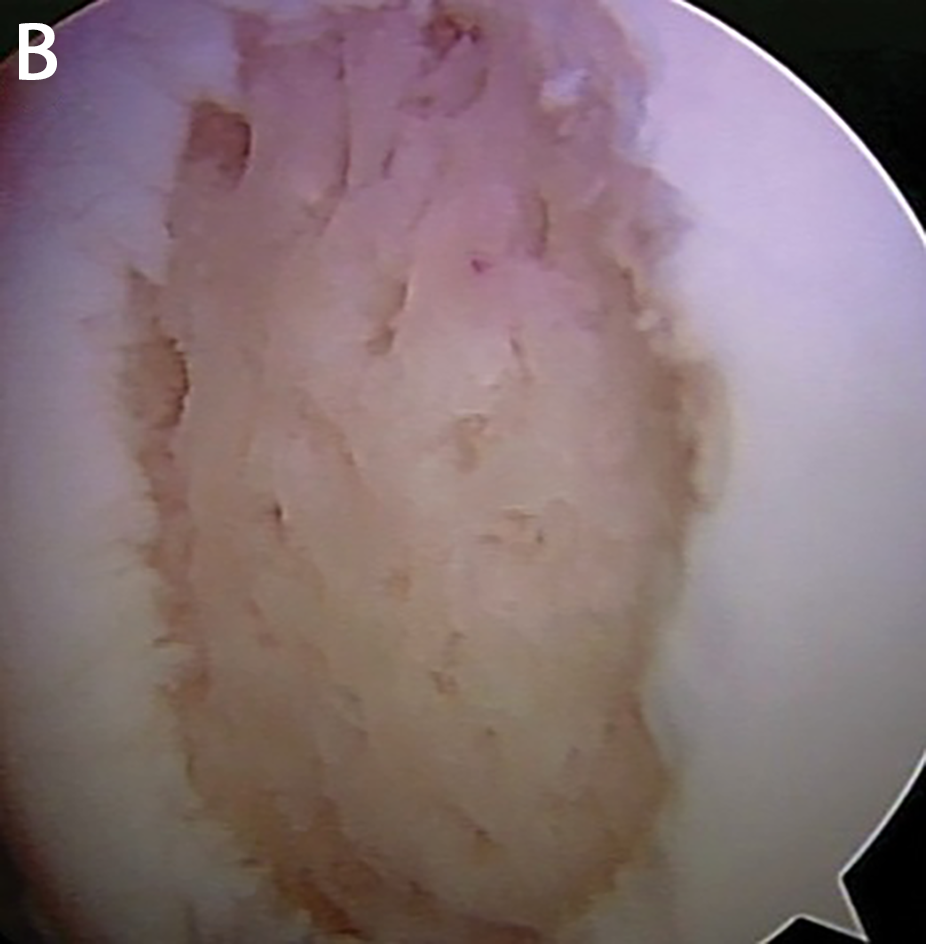

Diz ekleminde kıkırdak yaralanmasının artroskopik görüntüsü

Mikrokırık Yöntemi: Sınırlı ve 3 cm2’den küçük kıkırdak yaralanmasında uygulanan bir tedavi yöntemidir. Bu yöntemin avantajları tek bir ameliyat gerektirmesi ve artroskopi ile yapılmasıdır. Dezavantajı ise, oluşan tamir dokusunun kıkırdak benzeri olmasıdır. Yeni kıkırdak benzeri doku oluşana kadar, ameliyat sonrası altı-sekiz hafta eklem yüklenmeden korunmalıdır.

| A. Kıkırdak lezyonu ve B. Mikrokırık uygulaması | |